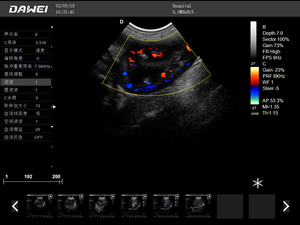

·支持彩色多普勒、頻譜多普勒、能量多普勒、連續多普勒等成像技術

·多倍波束成像技術幀頻提高同時,成像質量也能保證